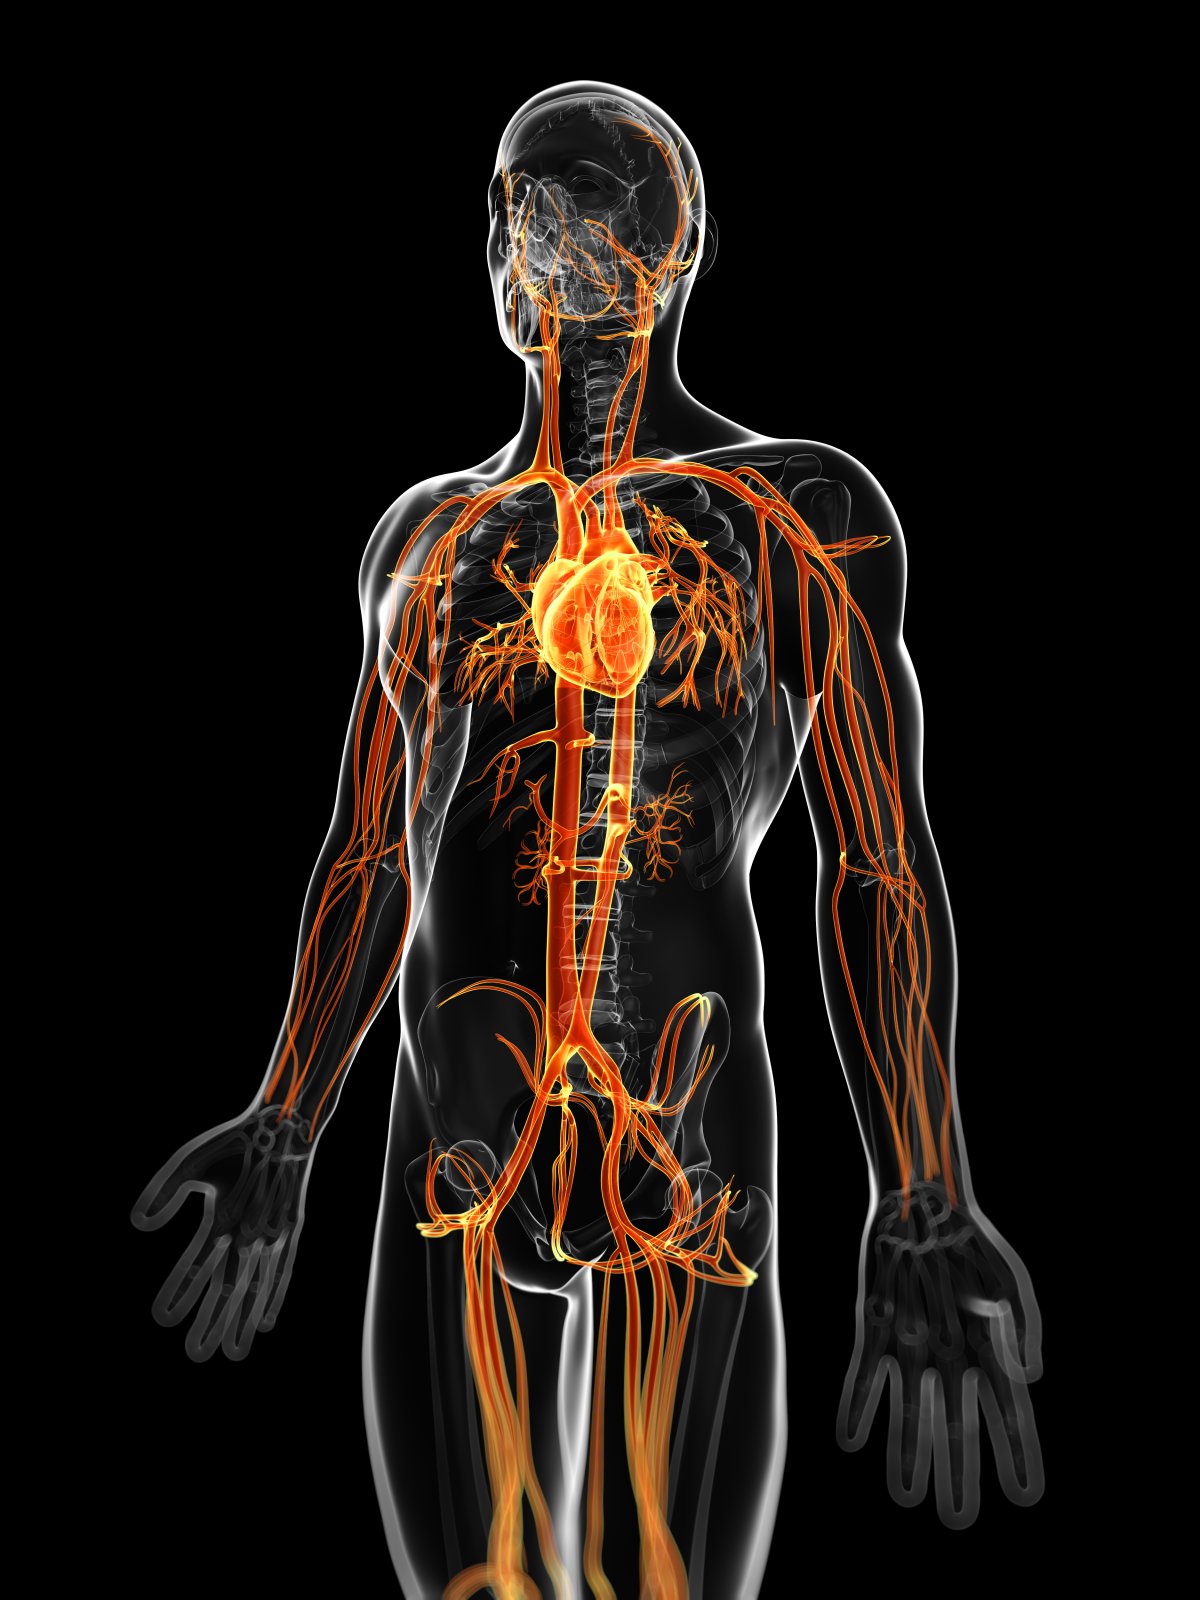

cévní soustava

Soubor trubic v těle živočichů a člověka, rozvádějící krev a mízu. U bezobratlých se objevuje jako uzavřený systém podélných cév u pásnic, kroužkovců, rypohlavců chapadlovek, ramenonožců a polostrunatců. Otevřenou cévní soustavu, kterou koluje krvomíza (herno lymfa), mají měkkýši, sumýšovci, drápkovci a členovci. Zvláštní stavbu má uzavřená cévní soustava ostnokožců. Cévní soustava hmyzu je otevřená. Hlavní částí je hřbetní céva, vzadu slepě končící. Skládá se ze srdce a dopředu vybíhající otevřené aorty. Pravidelně jsou součástí ještě hřbetní a břišní přepážka a přídatné pulsující orgány. Cévní soustava obratlovců se dělí na krevní soustavu, která je vždy uzavřená, a na neuzavřenou mízní soustavu. Viz také cévy; krevní oběh; mízní soustava.